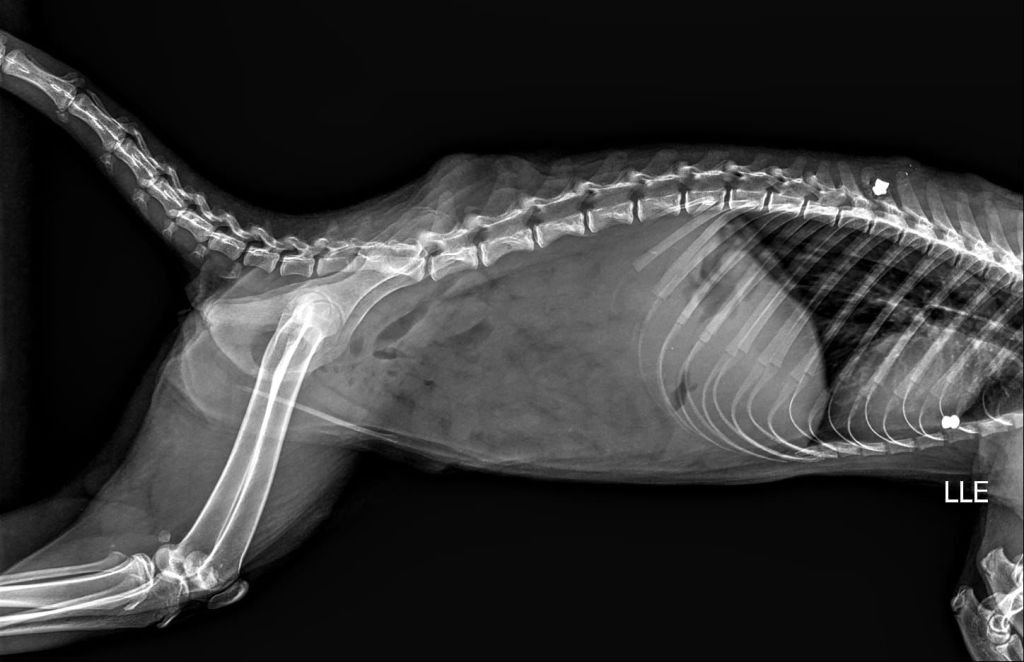

Além da preocupação ambiental, a Secretaria alerta para casos de maus-tratos registrados na região. Há relatos de quatis atingidos por disparos de espingarda de chumbo, incluindo uma fêmea com projéteis alojados no corpo, inclusive na região da coluna vertebral. Um dos casos está sendo acompanhado pela médica veterinária do Bosque Municipal, Dra. Melissa Campitelli, que, após exame de raio-x, identificou dois chumbinhos alojados no corpo de um dos animais.